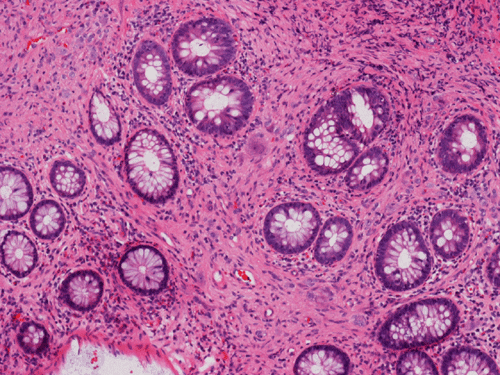

Clinical information The patient was a 54 year-old man. On screening colonoscopy, a small nodular polyp was found. The following are representative images from this polyp.

Pathology of the Case: The lesion is a small polypoid nodule of mucosa. At scanning magnification, there seems to be a mucosal flattening with erosion. There is focal reduction of glands and increased spacing in between glands (Panel A). Mucin production by the glandular epithelium is normal and there is no inflammatory cell infiltration (Panel B). There is no epithelial proliferation. On the other hand, the glands seems to be separated by spindle cells reminiscent of peripheral nerve(Panel B). On high magnification, there are some large neuronal or ganglionic appearing cell clusters in the lamina propria (Panel C). These neural tissue and ganglionic cells are positive for S100 protein (Panel D and E).

DIAGNOSIS: Solitary ganglioneuroma of colon.